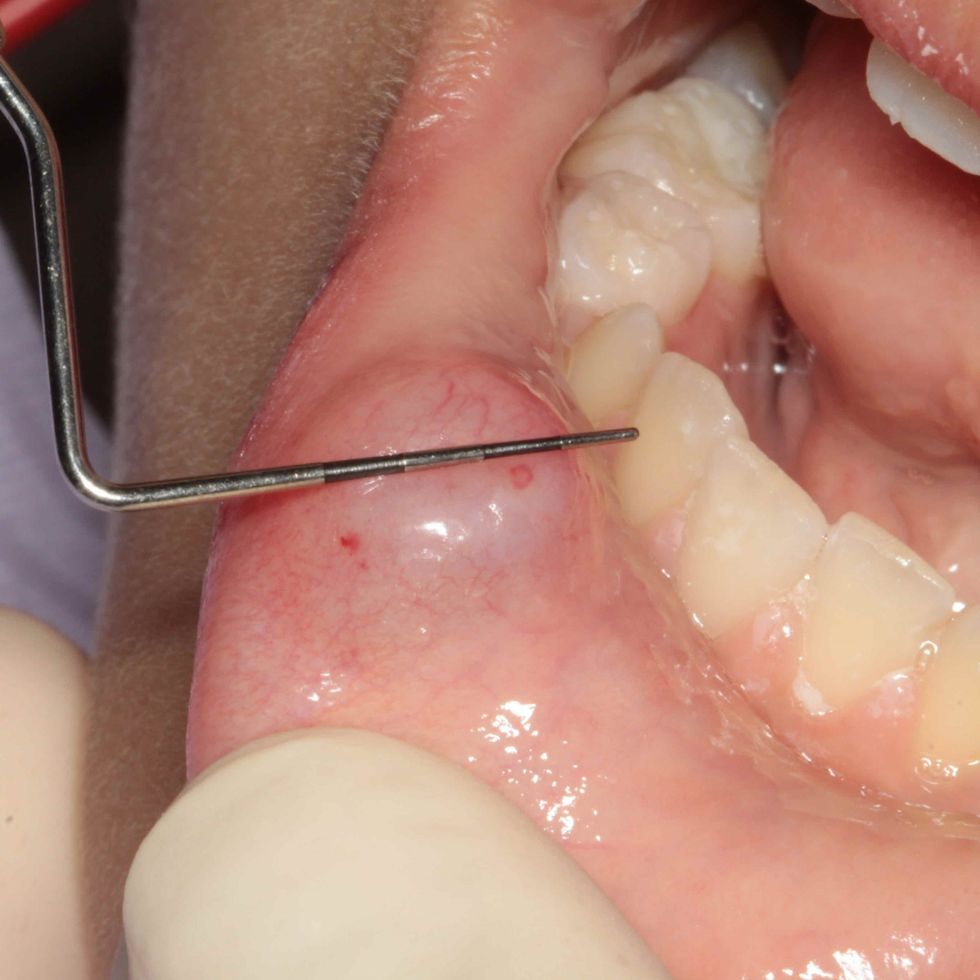

Një cist mukoz është i padëmshëm dhe është një ënjtje e mbushur me lëngje që i ngjan një flluske në gojë. Zakonisht ndodh në pjesën e brendshme të buzës. Simptoma e parë është shfaqja e një gunge në formën e një afte të kuqe, e cila zbardhet gjatë maturimit të saj dhe nëse nuk largohet vetë, formohet ky cist.

Cistet zakonisht zhvillohen kur gjëndrat e pështymës bllokohen me shumë mukus, por mund të ketë edhe shkaqe të tjera. Ky problem prek popullatën nga 10 deri në 25 vjeç, por mund të shfaqet tek personat e të gjitha moshave dhe të dy gjinive.

Më së shpeshti shkaktohen nga kafshimi i buzëve, kafshimi i pjesës së brendshme të faqes, komplikimet me piercing, lëndimet e gjëndrave të pështymës, kur dhëmbët ngjitur shkaktojnë dëmtim të mukozës, infeksionet orale ose reaksionet ndaj infeksioneve, higjiena e keqe orale.

Cistet sipërfaqësore shpesh zhduken vetë. Për të parandaluar infeksionin ose dëmtimin e indeve, mos u përpiqni kurrë hiqni cistet vet. Ato zakonisht hiqen me laser, krioterapi, duke injektuar kortikosteroide në cist për të reduktuar inflamacionin ose kirurgji, që është më e zakonshme.